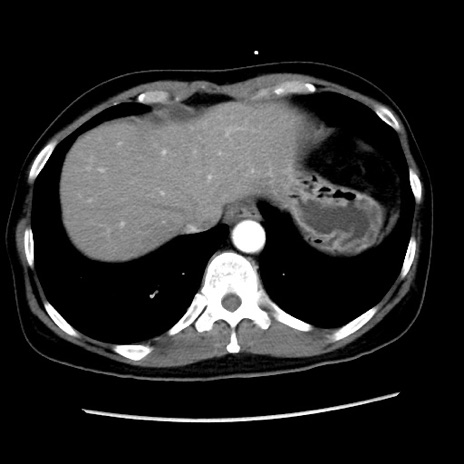

症例10(横断像)

【症例】 50歳代女性

【主訴】 腹痛

【現病歴】前日生レバーを食べた。今朝に排便あり。 昼前に突然発症の腹痛を生じ、当院救急外来を受診した。

【既往歴】 子宮筋腫にてで子宮全摘後

【身体所見】 意識清明、腹部:平坦、軟、下腹部やや左を中心に圧痛・反跳痛あり、筋性防御あり

【データ】WBC 7800、CRP 0.07